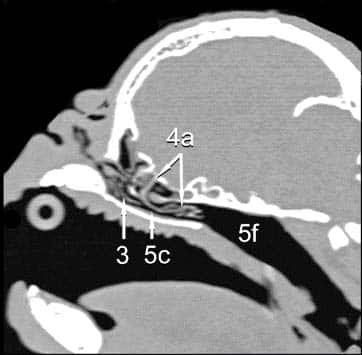

Die Beschwerden kurznasiger Hunde können bei warmen Umgebungstemperaturen dramatisch zunehmen und zum Kollaps führen. Die Ursache für die extreme Wärmeempfindlichkeit ist weniger eine unzureichende Belüftung der Lunge und damit eine Störung des Gasaustausches, sondern die unzureichende Nasenatmung dieser Tiere. Im Gegensatz zum Menschen braucht der Hund für die Regulation seines Wärmehaushalts unverzichtbar eine »funktionierende« Nase: Wenn es draußen heiß ist, beginnt der Mensch zu schwitzen. Dabei wird das Wasser der Schweißdrüsen auf der großen Oberfläche der Haut verteilt und verdunstet. So entsteht die »Verdunstungskälte«, die das Blut in der Haut herunterkühlt. Hunde können nicht schwitzen wie der Mensch, sie haben kaum Schweißdrüsen, Hunde hecheln. Aber auch sie nutzen das Prinzip der Verdunstungskälte. Sie haben ihre große Oberfläche innerhalb der Nase: ein anatomisches Wunderwerk von feinsten Nasenmuscheln (Abb. 1, Nr. 3). Durch diese Muscheln strömt auch beim Hecheln die Einatemluft und erzeugt auf der durch Drüsen befeuchteten Oberfläche die Verdunstungskälte. Brachyzephale Tiere haben derart verkleinerte und kaum belüftete Nasenmuscheln, dass die Thermoregulation nicht mehr funktionieren kann. Deswegen sind brachyzephale Tiere besonders wärmeempfindlich, oft bereits bei Temperaturen ab 19°C und nach Belastung dauert die Erholungszeit viele Stunden [3].